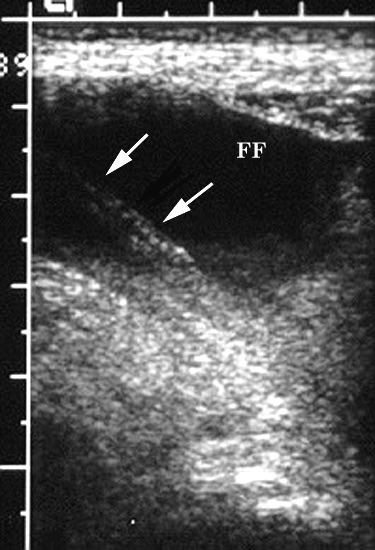

Figure 2. Transverse sonogram of the right lower

quadrant shows free fluid (arrows) adjacent to bowel

loops (B) |

Figure 3. Transverse pelvic US image at a lower level

than Figure 2 shows an appendicolith (large white arrow)

within the dilated appendix (small black arrows). Free

fluid (FF) is noted anteriorly. Note posterior acoustic

shadow (S) related to the appendicolith. |